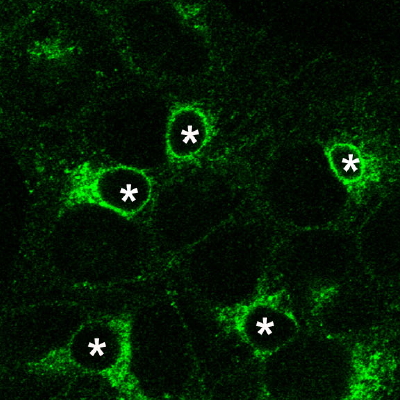

Figure 1 : Images par contraste de phase d’un épithélium de cellules WIF-B9 et par immunofluorescence de la protéine ATP7B excrétant le cuivre vers la bile dans ces cellules.

Ajout de 1 µM de CuSO4 au milieu de culture pendant 2 heures. La protéine encercle les canalicules et joue son rôle de détoxication en transférant le cuivre dans le canalicule.